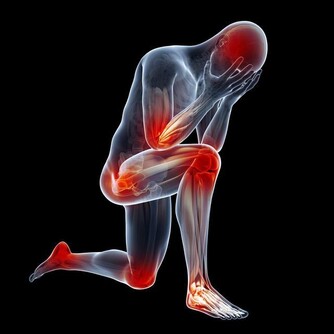

每天放屁8~20 次是正常的,但如果經常放屁不停,並伴有腹脹、排便障礙等情況,可能是「腸易激綜合徵」。

大人沒有屁放,腹部發脹如鼓,說明腹部脹氣,這就要考慮肛門直腸是否有毛病,如炎症、腫瘤、便秘、痔瘡等,必要時需肛門插管排氣。患有腸套疊、腸扭轉、腸梗阻無屁,是因為屁被腸子堵住。如果無屁放出並伴有劇烈的腸絞痛者,必須緊急到醫院求治,作為急診進行搶救處理。此外,胃穿孔、闌尾炎穿孔形成的腹膜炎,腹部發硬,觸之劇痛,也可無屁。新生兒不放屁,要檢查是否為無肛症或肛門發育不全。

由於屁中含有吲哚、硫化氫、氨等有害氣體,總是憋著不放, 就會引起腹脹、腹痛、頭痛、頭暈以及高血壓等症狀。一旦有屁, 還是放掉為宜, 但要注意遠離人群即可, 偷偷排出去就行。